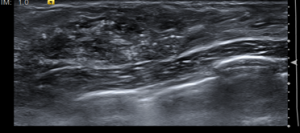

La ECO constituye el complemento ideal de la mamografía. Un nódulo sólido (fibroadenoma o cáncer) presenta la misma densidad radiológica que un nódulo líquido (quiste), por ello la ecografía permite distinguir sin problemas el contenido líquido del sólido. Sin embargo, tiene como limitación el hecho de que no es posible obtener una visión de toda la mama en una sola imagen. Pueden por tanto pasar fácilmente

desapercibidas lesiones pequeñas, La ecografía nos es útil para controlar la punta de la aguja en caso de punciones guiadas.

Mama hipoecogenica heterogénea con múltiples focos ecogénicos en relación con microcalcificaciones vistas en mamografía. lo anterior, se corresponde a un BIRADS 6, que se corresponde con un carcinoma ductal localmente avanzado con diagnóstico anatomopatológico.

DIAGNÓSTICO FINAL: CARCINOMA DUCTAL LOCALMENTE AVANZADO.